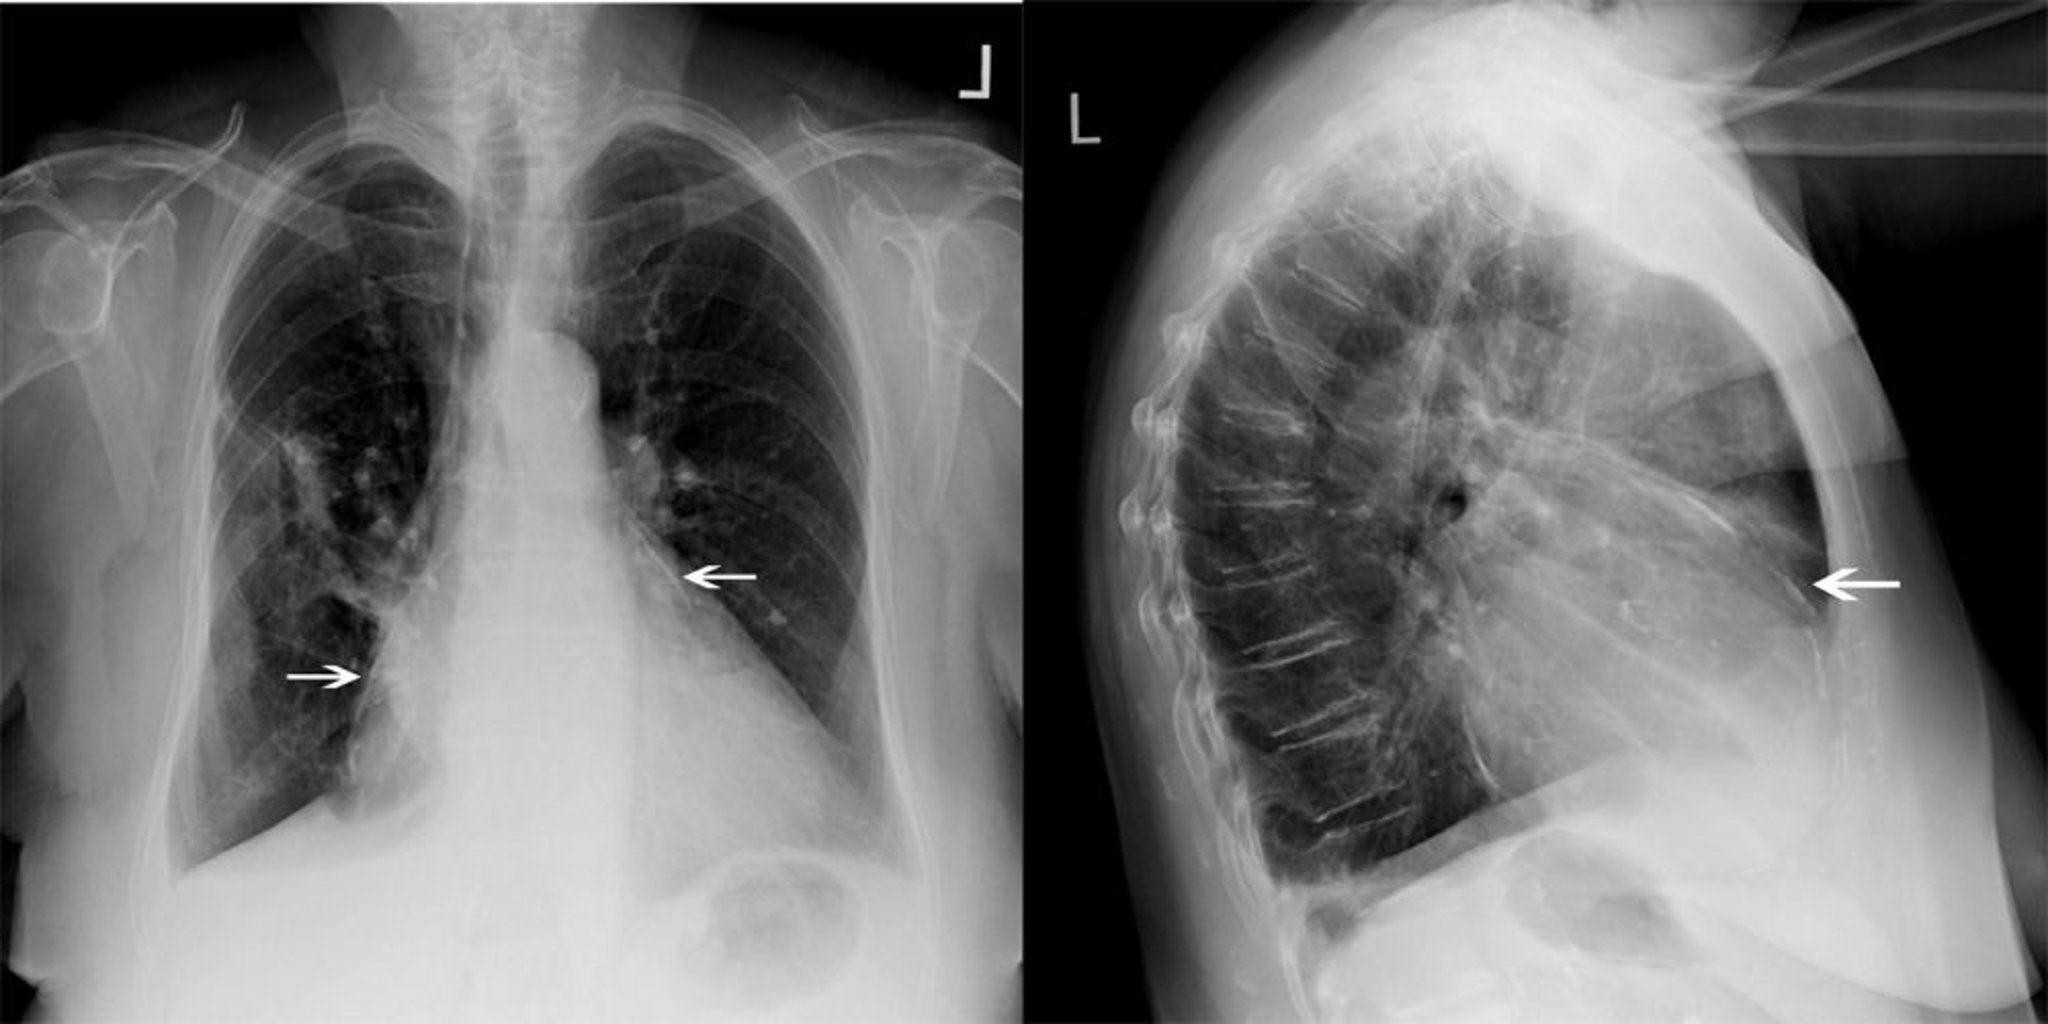

Radiografia do tórax de um paciente com pericardite constritiva

Esse paciente com pericardite constritiva apresenta calcificação pericárdica significativa (setas brancas).